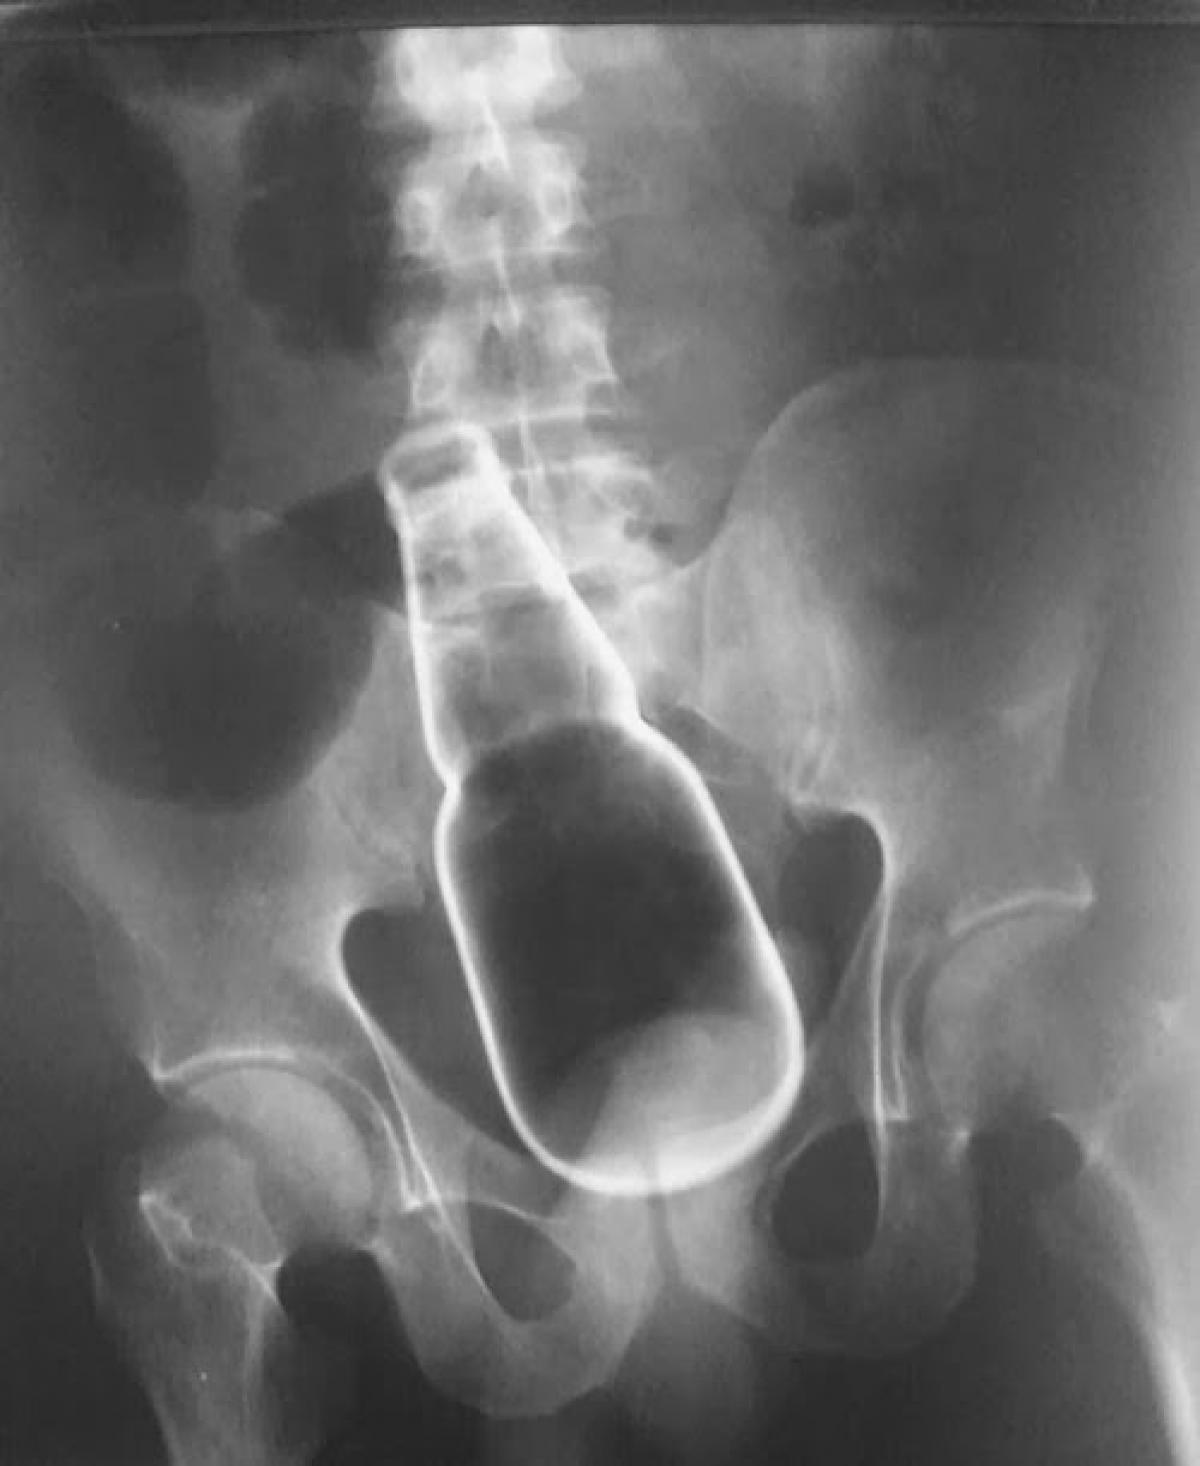

Razele X ne dovedesc că oamenii "pierd" adesea o mulțime de lucruri în propriul corp.

Cum ar fi de exemplu să uiți o sticlă de bere, un pistol sau cheile casei?